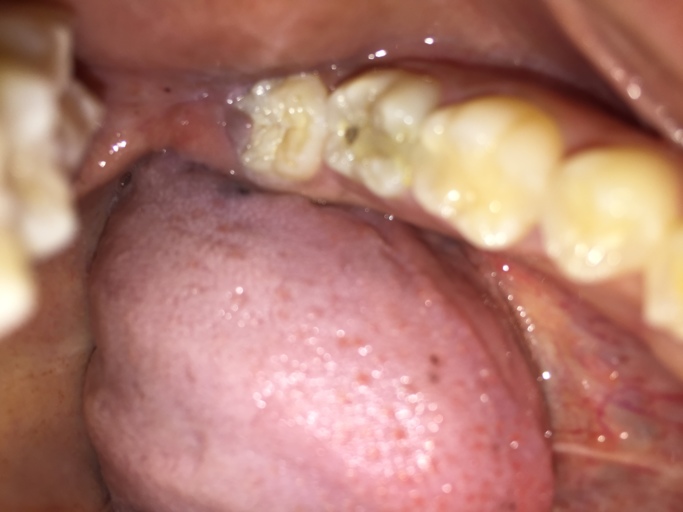

Big hole in tooth

I have a big hole in my tooth that just takes up the middle of my tooth. I don't want to have my tooth out as I have left it for a few weeks and Its going smaller, I want to know if I can have a filling and why is it getting smaller? I don't think there's a nerve it tooth anymore. P.s: there's no pain?

Unless you have had a root canal on the tooth, then the nerve is still there, however it can be necrotic. Once tooth structure is destroyed by the acid producing bacteria in your mouth, it does not grow back. Teeth cannot regenerate. The hole may appear as if it is getting smaller from the trapping of food and plaque which will continue to fill the hole and allow the decay process to continue to progress. It is important for you to not wait until there is pain. Rather, schedule and appointment with your dentist now to restore the tooth. Waiting will put you at risk of pain and will only allow the tooth to get worse and essentially cost you more money to restore.